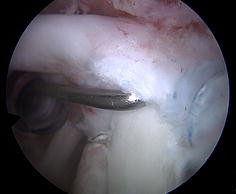

Fig. 3